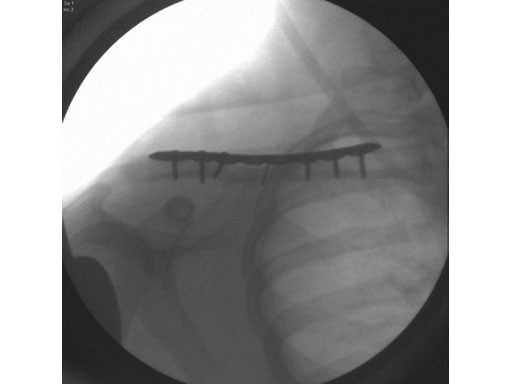

A 22-year-old man sustained an open clavicle fracture after a motorcycle injury.

Fig 2ab Postoperative images.